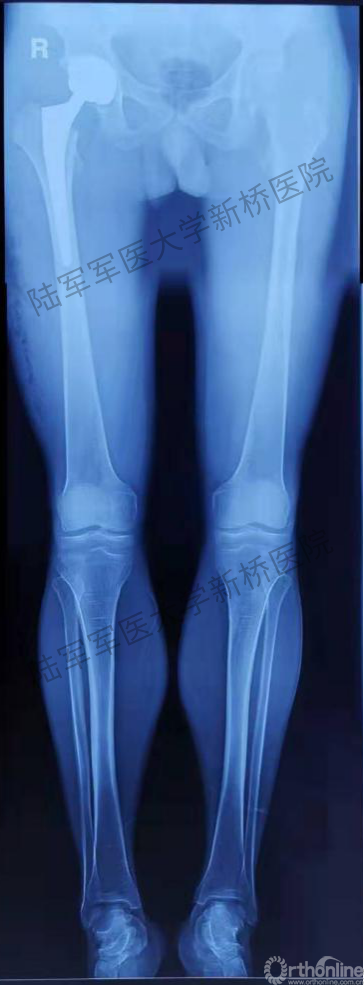

患者术后双下肢全长X片

为了最大程度地保留对髋关节软组织结构的完整性和张力状态,张瑗教授采用个人擅长的直接前入路(DAA)进行手术,此入路最大程度降低髋关节术后脱位风险,另外保障了人工关节假体的精准位置。手术切皮至安装假体耗时42分钟,术中出血约100ml,术中应用假体大小与AI HIP系统术前规划完全一致,高偏心距假体保证了关节周围软组织的张力。术后复位良好,假体稳定性佳。由于切口仅为9cm,疼痛刺激轻微,加之无任何管道的妨碍,如尿管、引流管、输液管等,和患者在康复医生指导下当日下地进行活动,主观感受极佳。这些也进一步映证了新桥医院骨科关节中心MDT团队常态化推进ERAS方案的确切效果!